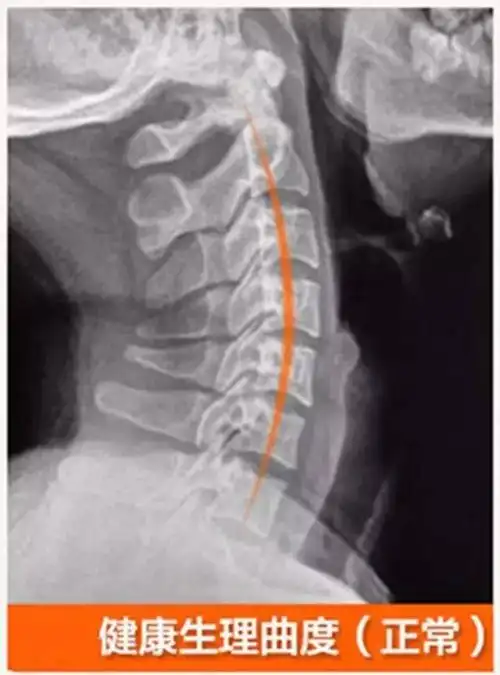

颈椎曲度直

人体正常的颈椎骨受生理需要,存在弯曲弧度.